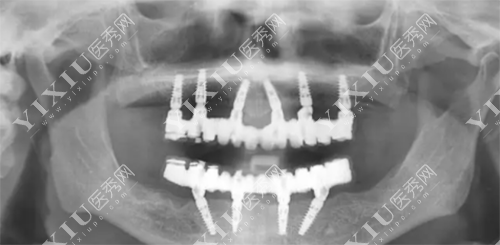

德国卡瓦种植体上部是方形螺纹中部是细方形螺纹,植体根尖部是V型螺纹,这种原创的螺纹可以减少牙槽骨的损伤,稳定比较好。

卡瓦种植体型号比较多,分别是ICE美学种植体、SPI螺旋形种植体、DFI双适应种植体、ATID超短种植体、ARROW超窄种植体这五种植体,种适应症比较广。